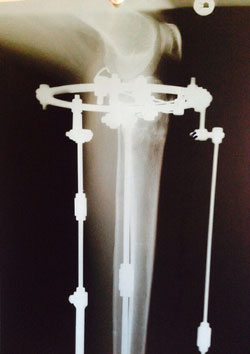

Дата операции 23.01.2015г.

Дата снятия аппаратов 28.04.2015г.

Срок лечения 95 дней.